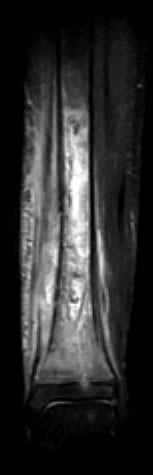

问题 男,33岁,有发热,小腿局部有疼痛,红肿并有压痛,请结合图像,选择最佳答案 ( )

选项 A、骨髓瘤 B、骨化性肌炎 C、脂肪瘤 D、未见异常 E、骨髓炎

答案 E